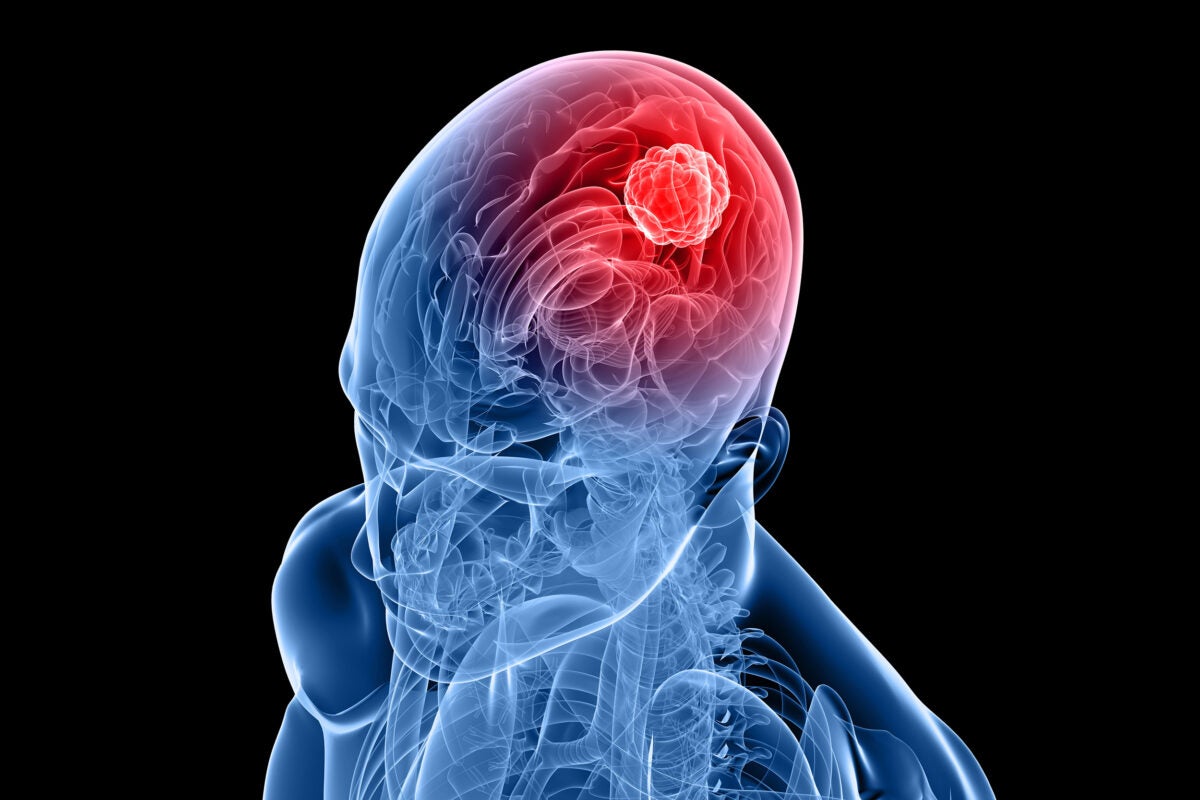

Breakthrough blood test developed for brain tumors — Harvard Gazette12 abril 2025

Breakthrough blood test developed for brain tumors — Harvard Gazette12 abril 2025 -